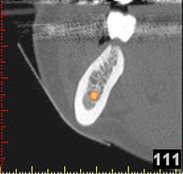

3D-Implantatplanung - Detailaufnahme 1

3D-Implantatplanung - Detailaufnahme 2

3D-Implantatplanung - Detailaufnahme 3

3D-Implantatplanung - Detailaufnahme 4

3D-Implantatplanung - Detailaufnahme 5

3D-Implantatplanung - Detailaufnahme 6

3D-Implantatplanung - Detailaufnahme 7

3D-Implantatplanung - Detailaufnahme 8

3D-Implantatplanung - Detailaufnahme 9